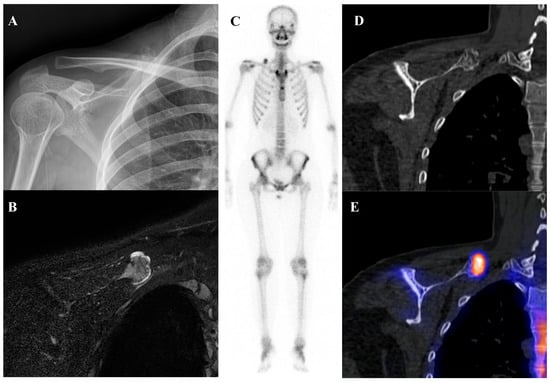

Osteoid osteoma is a small, benign bone-forming tumor that classically presents in young males with nocturnal pain relieved by nonsteroidal anti-inflammatory drugs. It has a pathognomonic appearance on a three-phase bone scan. Due to its highly vascular nidus and intense osteoblastic activity, the lesion demonstrates increased perfusion on flow images, hyperemia on blood pool images, and intense, focal uptake on delayed images [59]. This intense focal uptake on the delayed phase is often referred to as the “double-density sign,” characterized by a central hot spot of extreme avidity (the nidus) surrounded by a less intense but still avid zone of reactive sclerosis [60]. Bone scintigraphy has a sensitivity approaching 100% for detecting osteoid osteomas [61]. Although benign lesions may also demonstrate increased tracer uptake, reducing the specificity of this technique, the integration of SPECT/CT substantially enhances diagnostic accuracy by providing precise anatomic localization and improved lesion characterization [62]. It is particularly valuable for localizing small or intra-articular lesions that may be occult or difficult to identify on plain radiographs. While [18F]FDG PET/CT usually shows high metabolic activity in the nidus [63], some osteoid osteomas demonstrate no uptake [64]. Despite this variability, [18F]FDG PET/CT can be useful for assessing treatment response [65]. Figure 4 shows an osteoid osteoma of the femoral neck, where bone scintigraphy and SPECT/CT clearly identified the nidus with intense uptake in concordance with MRI findings.

Figure 4.

An 11-year-old male with osteoid osteoma of the left femoral neck. (A) T2-weighted fat-suppressed magnetic resonance imaging shows a lesion with high signal intensity and a sclerotic rim in the medial cortex, accompanied by perilesional edema (“half-moon sign”). (B,C) Bone scintigraphy demonstrates increased uptake in the left femoral neck on both blood pool and delayed phases. (D–G) Bone single-photon emission tomography/computed tomography reveals an osteolytic lesion with a central nidus and intense uptake.